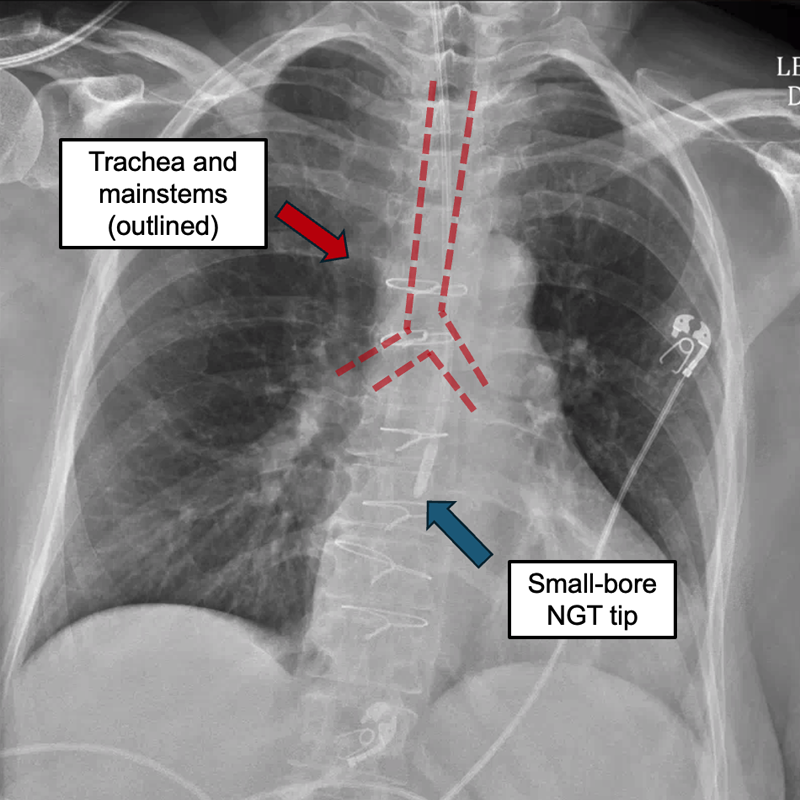

Annotated chest X-ray with NGT placed

Sorry! This one is close. We can tell that the NGT cuts straight across the proximal left mainstem bronchus and continues down. So, it's in the esophagus and not airways/lungs! However, the tip is still not past the G-E junction, nor is it below the diaphragm. We need to advance this further. (For this patient, this was actually intentional as part of a two-step process for advancing the tube.)

Correct! The NGT does not cross through the GE-junction nor cross below the diaphragm. It does, at least, clearly bisect the proximal left mainstem bronchus rather than follow the lumen within, which means it's in the esophagus and not airway.